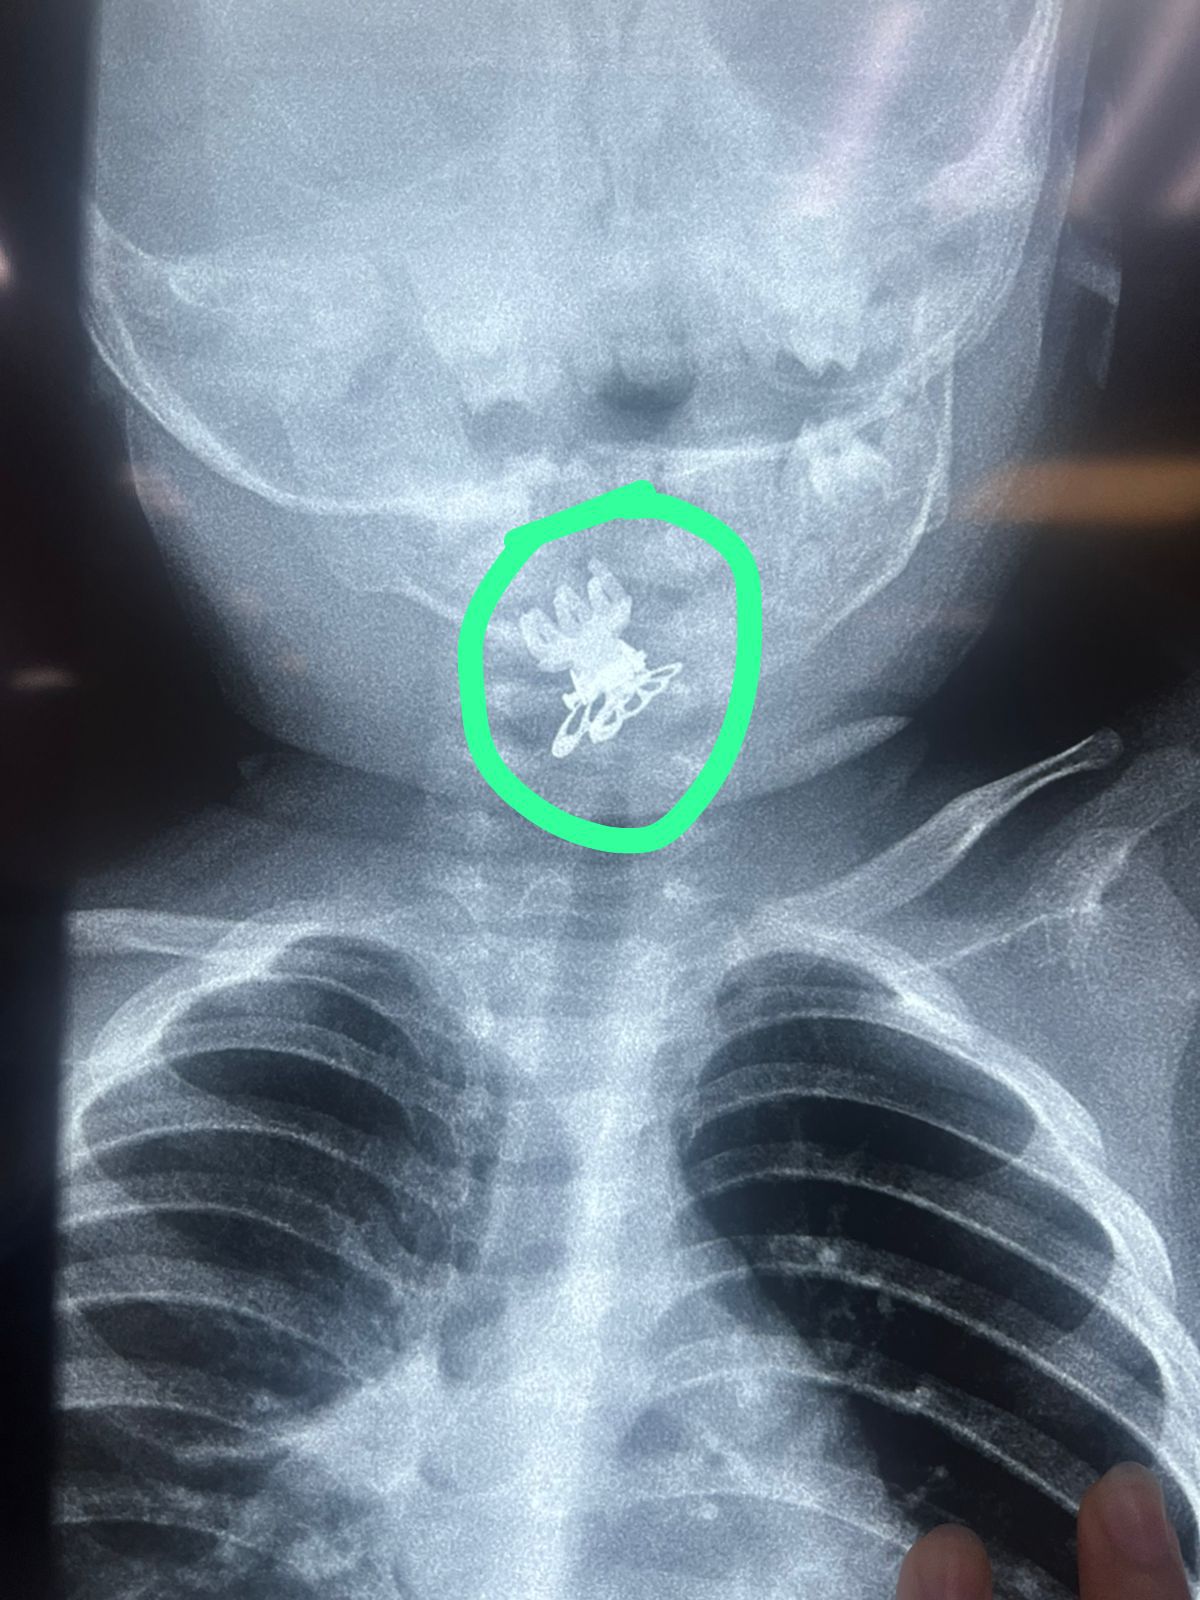

تمكّن فريق طبي في مدينة الصدر الطبية من إنقاذ حياة طفلة بعمر سنة ونصف بعد تعرضها لحالة اختناق شديدة نتيجة ابتلاعها مشبك شعر (قرّاصة) استقر في مدخل المجرى التنفسي.

وأوضحت الطبيبة الاختصاص جراحة الأنف والأذن والحنجرة الدكتورة فرقان حميد محمد” أن الطفلة أُدخلت إلى صالة عمليات الطوارئ وهي تعاني من اختناق وسعال شديدين وعلى الفور تم إجراء الفحوصات والأشعة اللازمة التي أظهرت وجود جسم غريب في مدخل المجرى التنفسي.